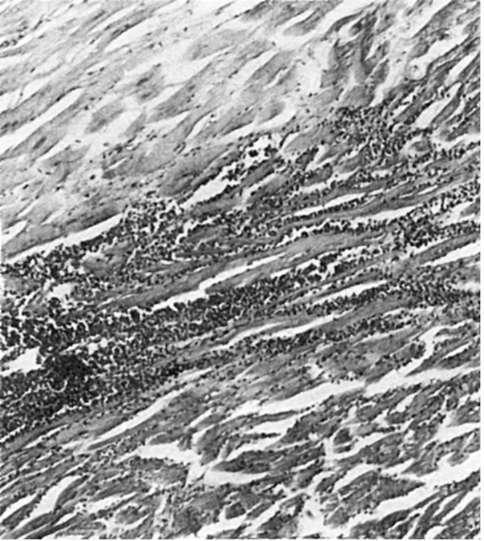

Рис. 160. Инфаркт миокарда. Участок некроза (вверху) отграничен от сохранившегося миокарда (внизу) зоной демаркационного воспаления

ского ряда. Макрофаги принимают участие в резорбции некротических масс, в их цитоплазме появляются липиды, продукты тканевого детрита. Фибробласты, обладая высокой ферментативной активностью, участвуют в фибриллогенезе. Организация инфаркта происходит как из зоны демаркации, так и из «островков» сохранившейся ткани в зоне некроза. Этот процесс продолжается 7-8 нед, однако эти сроки подвержены колебаниям в зависимости от размеров инфаркта и реактивности организма больного. Новообразованная соединительная ткань вначале рыхлая, типа грануляционной, затем созревает в грубоволокнистую рубцовую, в которой вокруг сохранившихся сосудов видны островки гипертрофированных мышечных волокон. В полости перикарда в исходе фибринозного перикардита появляются спайки. В них нередко образуются сосуды, анастомозирующие с внесердечными коллатералями, что способствует улучшению кровоснабжения миокарда. Таким образом, при организации инфаркта на его месте образуется плотный рубец. В таких случаях говорят опостинфарктном крупноочаговом кардиосклерозе. Сохранившийся миокард, особенно по периферии рубца, подвергается регенерационной гипертрофии.